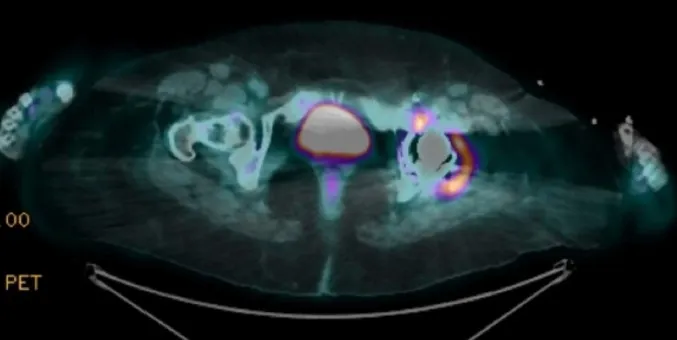

O **PET-CT** (imagem abaixo) revela hipercaptação no quadril operado, adenopatia ilíaca e foco nodular em reto abdominal: inflamação “acendendo” onde houve vazamento de cimento. O filme mental começa a focar: **reação sarcoide-like induzida por adjuvante?**

* **Imagem com mapa da inflamação**: PET-CT positivo no sítio da prótese e cadeias linfáticas adjacentes.